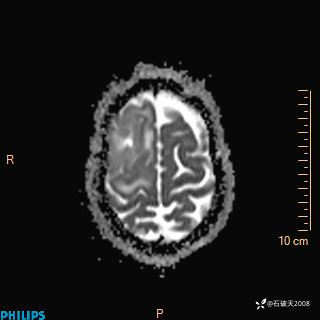

2024.2.21MR

ADC